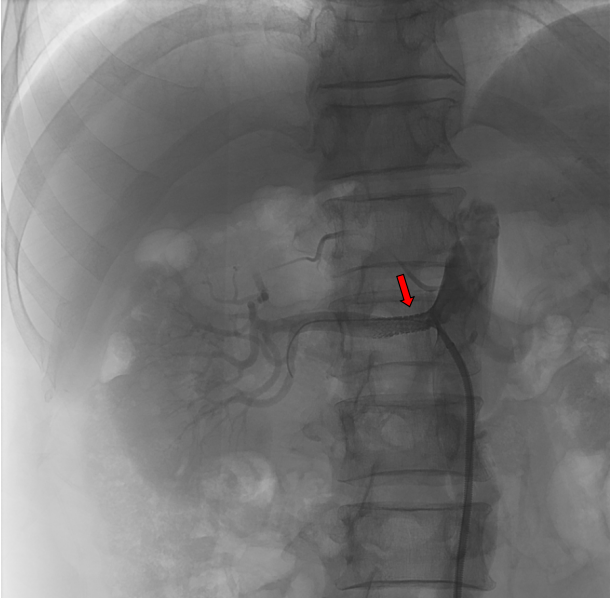

红色标记为支架置入后,狭窄解除

患者于4月9日上午送介入手术室行右肾动脉支架置入术。术中造影显示右肾动脉起始段明显狭窄,狭窄约90%,予置入肾动脉裸支架(7*19mm)后,造影显示右肾动脉狭窄解除,支架扩张良好,右肾灌注恢复。